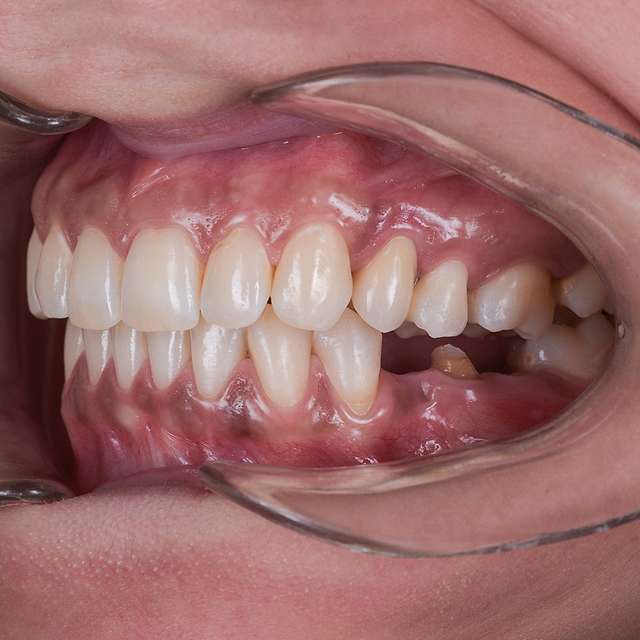

For optimal esthetic results, the final design must always be the refference for the surgery. This design together with the CBCT of the patient are compiled to find the ideal position of the dental implants.

Guided surgery is safe and precise. A surgical guide is recommended in difficult or complex cases, to minimise risks and complications.